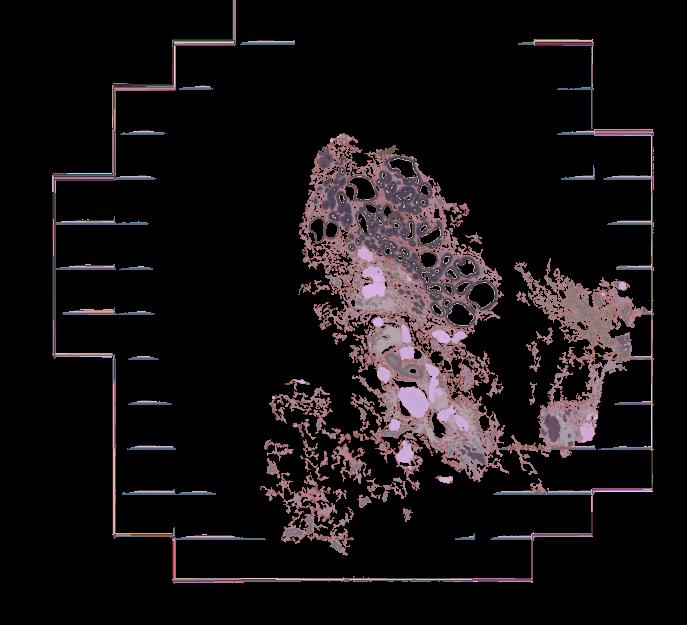

Atlas: Washington University

Breast cancer (BC) is defined by distinct molecular subtypes with different cells of origin. The transcriptional networks that characterize the subtype-specific tumor-normal lineages are not established. In this work, we applied bulk, single-cell and single-nucleus multi-omic techniques as well as spatial transcriptomics and multiplex imaging on 61 samples from 37 patients with BC to show characteristic links in gene expression and chromatin accessibility between BC subtypes and their putative cells of origin. Regulatory network analysis of transcription factors underscored the importance of BHLHE40 in luminal BC and luminal mature cells and KLF5 in basal-like tumors and luminal progenitor cells. Furthermore, we identify key genes defining the basal-like (SOX6 and KCNQ3) and luminal A/B (FAM155A and LRP1B) lineages. Exhausted CTLA4-expressing CD8+ T cells were enriched in basal-like BC, suggesting an altered means of immune dysfunction. These findings demonstrate analysis of paired transcription and chromatin accessibility at the single-cell level is a powerful tool for investigating cancer lineage and highlight transcriptional networks that define basal and luminal BC lineages.